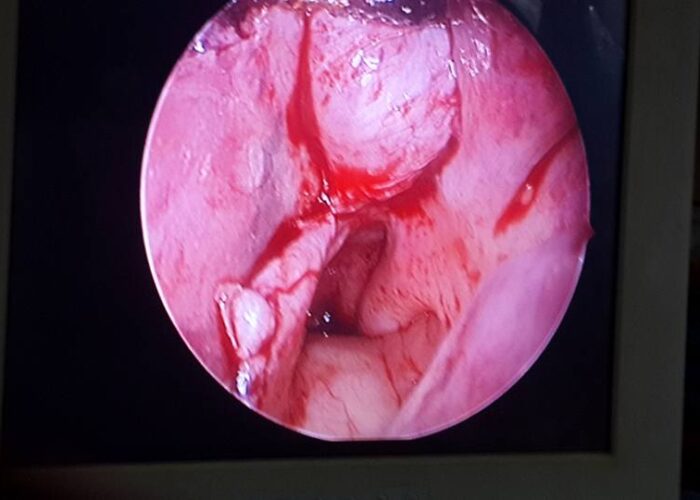

3 Endoscopic Pituitary Cases in Manik Hospital